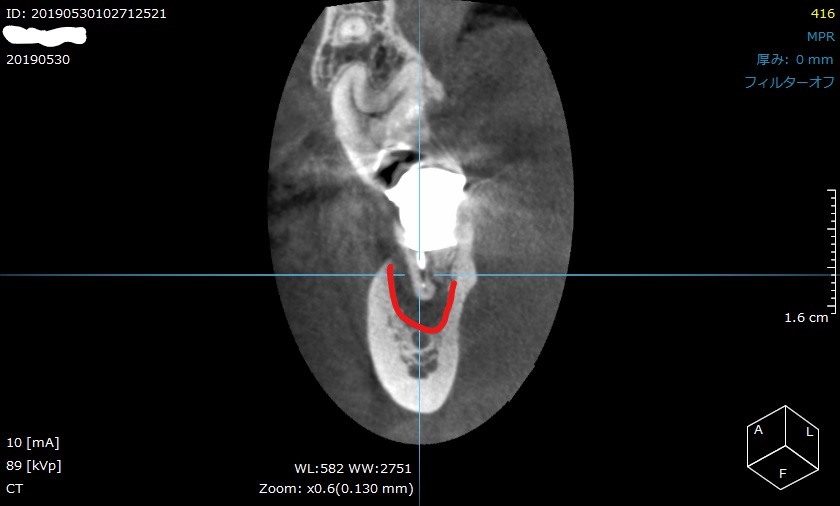

CT撮影の画像です。

CT撮影は、様々な方向から歯を立体的に確認することができます。

つまり3Dですね。

正面から見ても、赤枠の場所が黒く抜けています。

CT撮影で、膿んで骨が溶けている範囲が詳細に分かります。